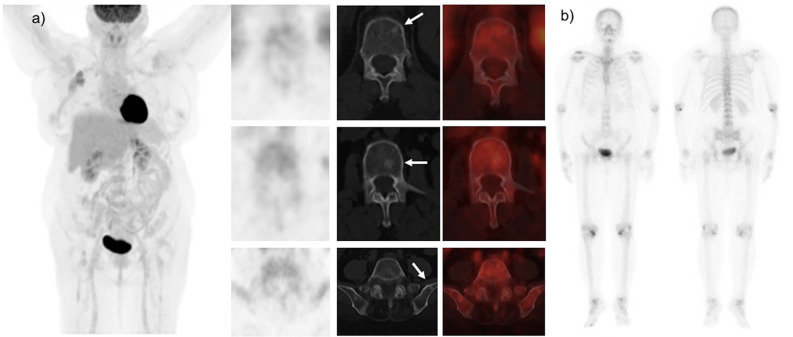

通过影像学识别骨转移是必要的,对小叶乳腺癌患者可能具有挑战性。我们报告了一位66岁的小叶性乳腺癌患者,她接受了18F-氟脱氧葡萄糖正电子发射断层扫描/计算机断层扫描(FDG PET/CT)进行分期。18F-FDG PET/CT显示原发肿瘤细胞中FDG摄取极少。脊柱和骨盆骨可见明显的硬化性病变,FDG密度低。随后的Tc-99m二膦酸亚甲基骨扫描结果并不显著。磁共振多重成像(MRI)显示骨转移。MRI对浸润性小叶癌可能是有益的。当18F-FDG PET/CT评估可能困难且受限时,MRI有助于改善转移性评估,特别是在仅骨和骨为主的转移性恶性肿瘤中。

Identifying osseous metastases by imaging is essential and may be challenging in patients with lobular breast cancer. We present a case of a 66-year-old woman with lobular breast cancer who underwent 18F- fluorodeoxyglucose positron emission tomography/computed tomography (FDG PET/CT) for staging purposes. 18F-FDG PET/CT reveals minimal FDG uptake in the primary tumor cells. Prominent sclerotic lesions with low FDG avidity are seen in the spinal and pelvic bones. The subsequent Tc-99m methylene diphosphonate bone scan is unremarkable. The magnetic resonance imaging (MRI) reveals bone metastases. MRI may be beneficial in invasive lobular carcinoma. MRI facilitates improved metastatic evaluation, especially in bone-only and bone-predominant metastatic malignancies, when assessment with 18F-FDG PET/CT may be difficult and constrained.